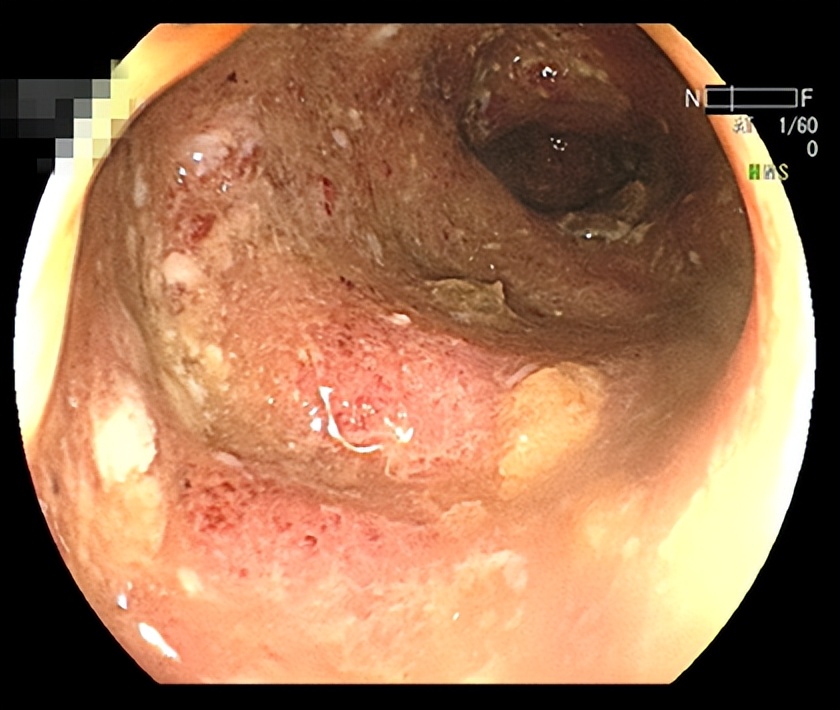

一个20多岁的年轻姑娘,很难想像她的肠道竟然是这样的:

据姑娘所述,她患有腹痛、腹泻、粘液脓血便,已经7、8年了,久治未愈,饱受折磨,甚至想做手术把坏掉的肠子切除。

经过检查,姑娘患有炎症性肠病,这种病很难根治,容易反复发作,需要长期用药,治疗效果不佳,严重影响患者生活质量,但因其没有典型的肿瘤结构,不会对寿命产生明显影响,故被称之为“绿色癌症”。